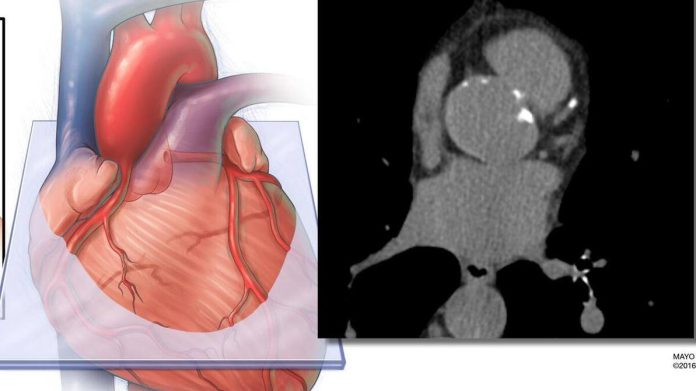

El estudio realizó un seguimiento de casi 12.000 adultos durante aproximadamente 16 años. Los investigadores aplicaron IA a las tomografías estándar de calcio en arterias coronarias de los participantes para medir la grasa que rodea el corazón. Compararon el valor predictivo de esta medición, tanto de forma independiente como en combinación, con dos enfoques estándar de evaluación del riesgo: la ecuación PREVENT de la American Heart Association, que incorpora factores tradicionales como edad, sexo, presión arterial, colesterol, diabetes y otras variables, y la puntuación de calcio en arterias coronarias, que cuantifica la placa calcificada en las arterias coronarias.

Los hallazgos muestran que el volumen de grasa cardíaca podría utilizarse de forma independiente para predecir eventos cardiovasculares. Además, mejoró de manera significativa la precisión global de la predicción del riesgo a largo plazo cuando se combinó con la puntuación de calcio coronario y la ecuación PREVENT, especialmente entre pacientes clasificados en categorías de bajo riesgo.

La cuantificación del calcio en arterias coronarias se utiliza ampliamente para evaluar el riesgo cardiovascular. Este estudio demuestra que puede extraerse información adicional de la misma exploración sin necesidad de pruebas adicionales ni costes añadidos.